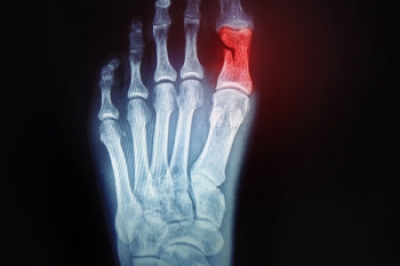

Dr. Kenneth Williams is a board-certified podiatrist with over three decades of experience. He is known to be thorough, and will always try to treat his patients conservatively. He has helped patients with all kinds of foot and ankle conditions, such as: foot pain, plantar fasciitis and other forms of heel pain, ingrown toenails, diabetic foot care and limb salvage, and more. As a highly skilled podiatric surgeon, Dr. Williams offers surgical solutions when necessary, such as advanced minimally invasive surgery (MIS) for the correction of painful bunions.